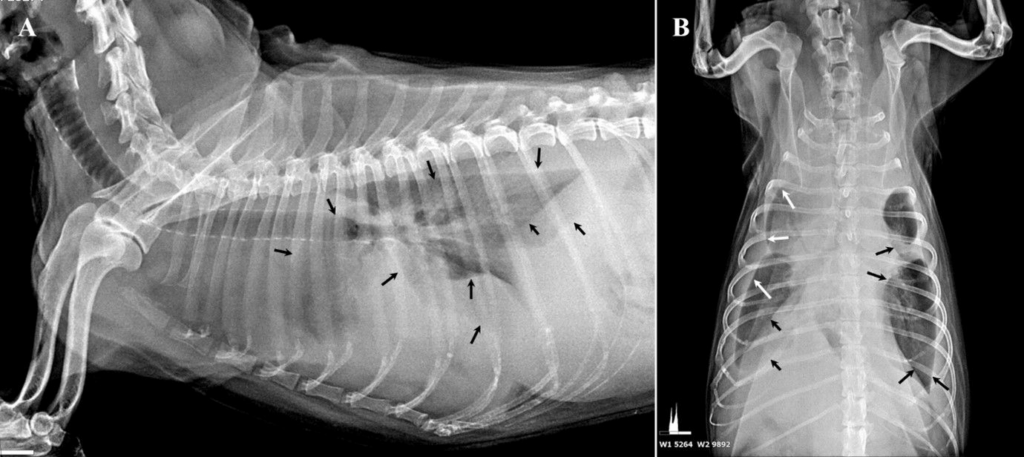

Fig. 2. 본 증례의 흉부 방사선 영상

폐엽 사이 간극(검은색 및 흰색 화살표)에서 방사선 투과도의 차이가 관찰되었으며, 이는 흉수를 시사하는 소견입니다. (A) 우측 측면 영상 / (B) 복배(DV) 영상

(Radiographic images of this case. Interlobular fissures (black and white arrows) showing differences in radiolucency suggestive of pleural effusion are observed.

(A) Right lateral view

(B) Ventro-dorsal view ))